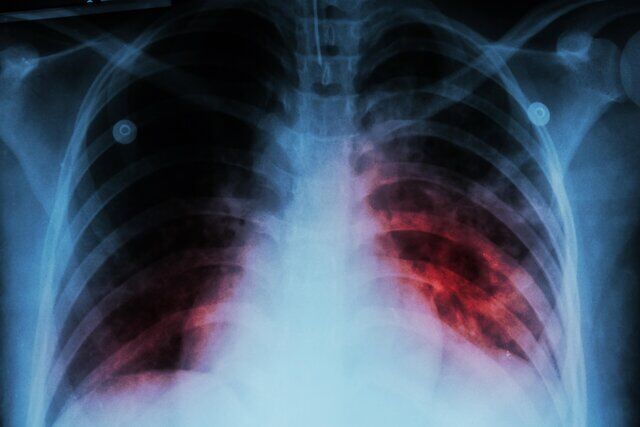

قباد مرادی اظهار داشت: برآورد سازمان جهانی بهداشت از میزان بروز سل در کشور حدود ۱۱ مورد به ازای هر ۱۰۰ هزار نفر جمعیت است.

وی افزود: بر اساس دادههای ثبتشده، میزان کشف موارد سل در کشور بین ۷ تا ۸ در هر ۱۰۰ هزار نفر است. هنوز پاسخ قطعی به این پرسش که آیا برآورد سازمان جهانی بهداشت دقیقتر است یا میزان شناسایی ما کمتر از واقعیت است، مشخص نشده و در حال بررسی هستیم تا به پاسخ علمی و قطعی برسیم.

مرادی با اشاره به وضعیت کنترل بیماری سل در ایران، گفت: حتی اگر همان برآورد ۱۱ در ۱۰۰ هزار نفر را ملاک قرار دهیم، در مقایسه با کشورهای همسایه، ایران یکی از بهترین عملکردها را در زمینه کنترل بیماری سل دارد. تنها یکی دو کشور از حاشیه خلیج فارس با جمعیت کمتر در این زمینه شرایط بهتری دارند که طبیعتا کنترل بیماری در جمعیتهای محدود سادهتر است.

رئیس مرکز مدیریت بیماریهای واگیر وزارت بهداشت افزود: در شرق کشور، دو کشور همسایه با یکی از بالاترین میزان بروز سل در جهان قرار دارند و یکی از آنها تخمینی بیش از ۲۰۰ مورد به ازای هر ۱۰۰ هزار نفر جمعیت دارد. با توجه به وجود حدود ۵ میلیون نفر مهاجر از این کشورها در ایران، حفظ این سطح از کنترل بیماری، دستاوردی بسیار ارزشمند برای نظام سلامت محسوب میشود.

مرادی خاطرنشان کرد: اگر بتوانیم اثبات کنیم که میزان بروز سل در کشور به کمتر از ۱۰ مورد در ۱۰۰ هزار نفر رسیده است، بر اساس تعریف جهانی حذف سل، ایران در جمع کشورهای پیشرو و موفق دنیا در کنترل این بیماری قرار خواهد گرفت.